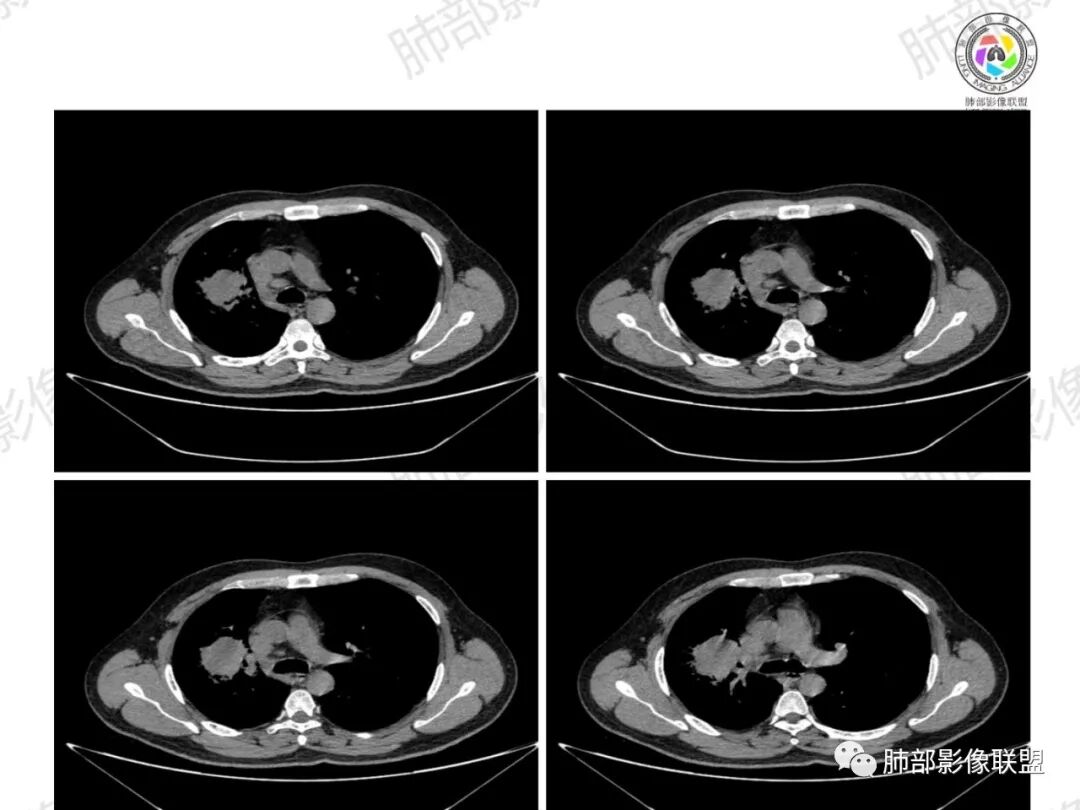

1、坏死区内寸草不生;2、病灶环形强化;3、远端树芽和结节;4、远端不是阻塞性炎症,而是树芽和结节,右肺上叶前后段都有,后段为主,而堵塞的支气管应该是前段;这些树芽的位置不是堵塞支气管的责任区;5、支气管不是突然截断堵塞,而是逐渐狭窄;6、纵隔淋巴结是椭圆形增大,内有坏死,不是肿瘤的圆形饱满;7、支气管周围粘液样坏死,符合仙人掌结核改变;

8、右侧胸廓塌陷。

2、湖泊样坏死:这个病例其实不是湖泊样坏死。湖泊样坏死边界不清,周围有水草样改变;这个病例的坏死更像水库,不是湖泊,坏死区边界清楚,里面寸草不生;

3、阻塞性炎症:这个病例远端的散在病灶分布与责任支气管不符,所以不是阻塞性炎症,应该是树芽;

4、纵隔淋巴结肿大:这个病例的淋巴结肿大,不是圆形饱满,而是椭圆形,中间坏死。

所以,这个病例应先考虑炎性病变,以结核可能性大。慢性非特异性炎症伴脓肿形成,也可以这样的影像改变,但解释不了周围的树芽和结节。

再解释一下水库与湖泊的区别:

水库:是人工的,边缘是石头彻的大坝(环形强化类似大坝),坝缘没草长,边界清楚。

湖泊:是天然的,周围没有环形强化的大坝,是逐渐过渡到强化区的,边缘可有细小血管或者坏死不彻底的肿瘤区。